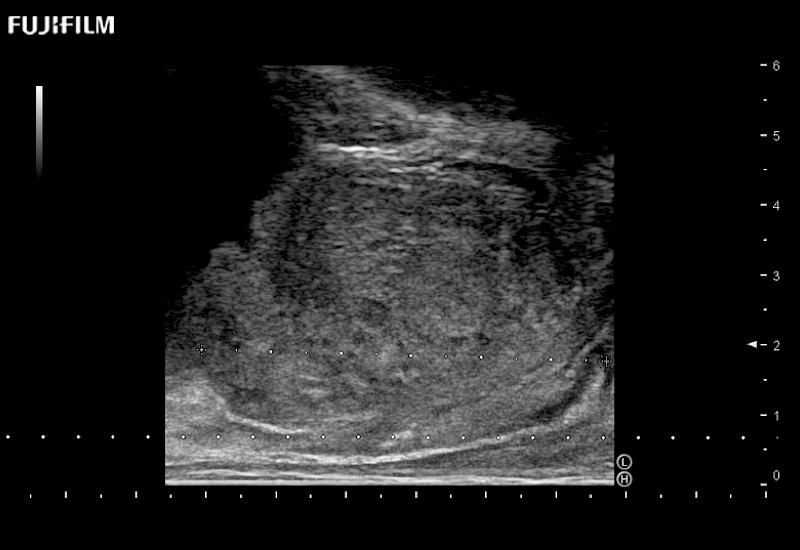

Exclusive 200° FOV end-fire prostate biopsy transducer.

Main Specifications:

Provides real-time imaging of both the sagittal and transverse planes